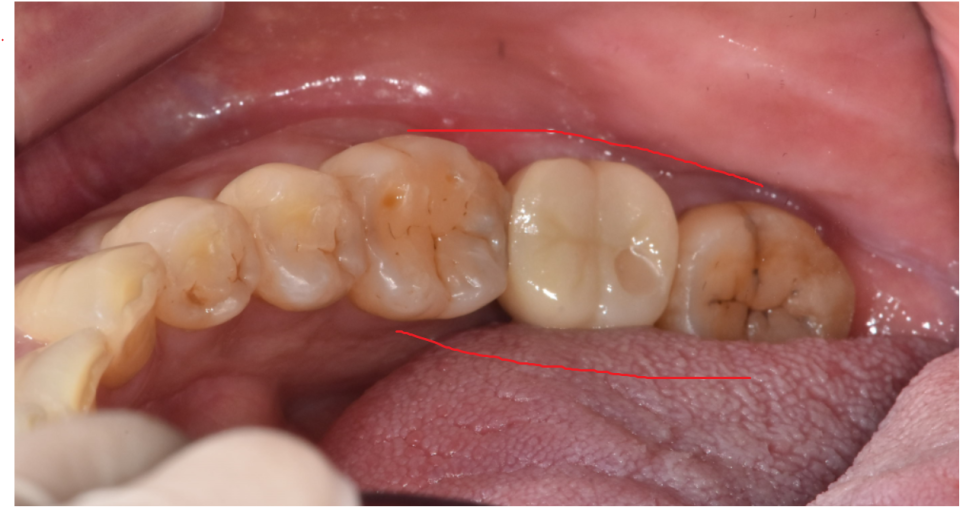

하부 어금니 손상

아래 치아가 팝콘 먹다가 깨졌다고

도움을 요청하신 환자분입니다.

그 이전에도 몇번 시큰 시큰 하긴 했어요.

입안을 먼저 살펴보았는데요.

치아의 절반 가까이 깨져 나갔네요.

손상된 치아 상태가

육안으로도 거뭇 거뭇한게

충치가 확인되었습니다.